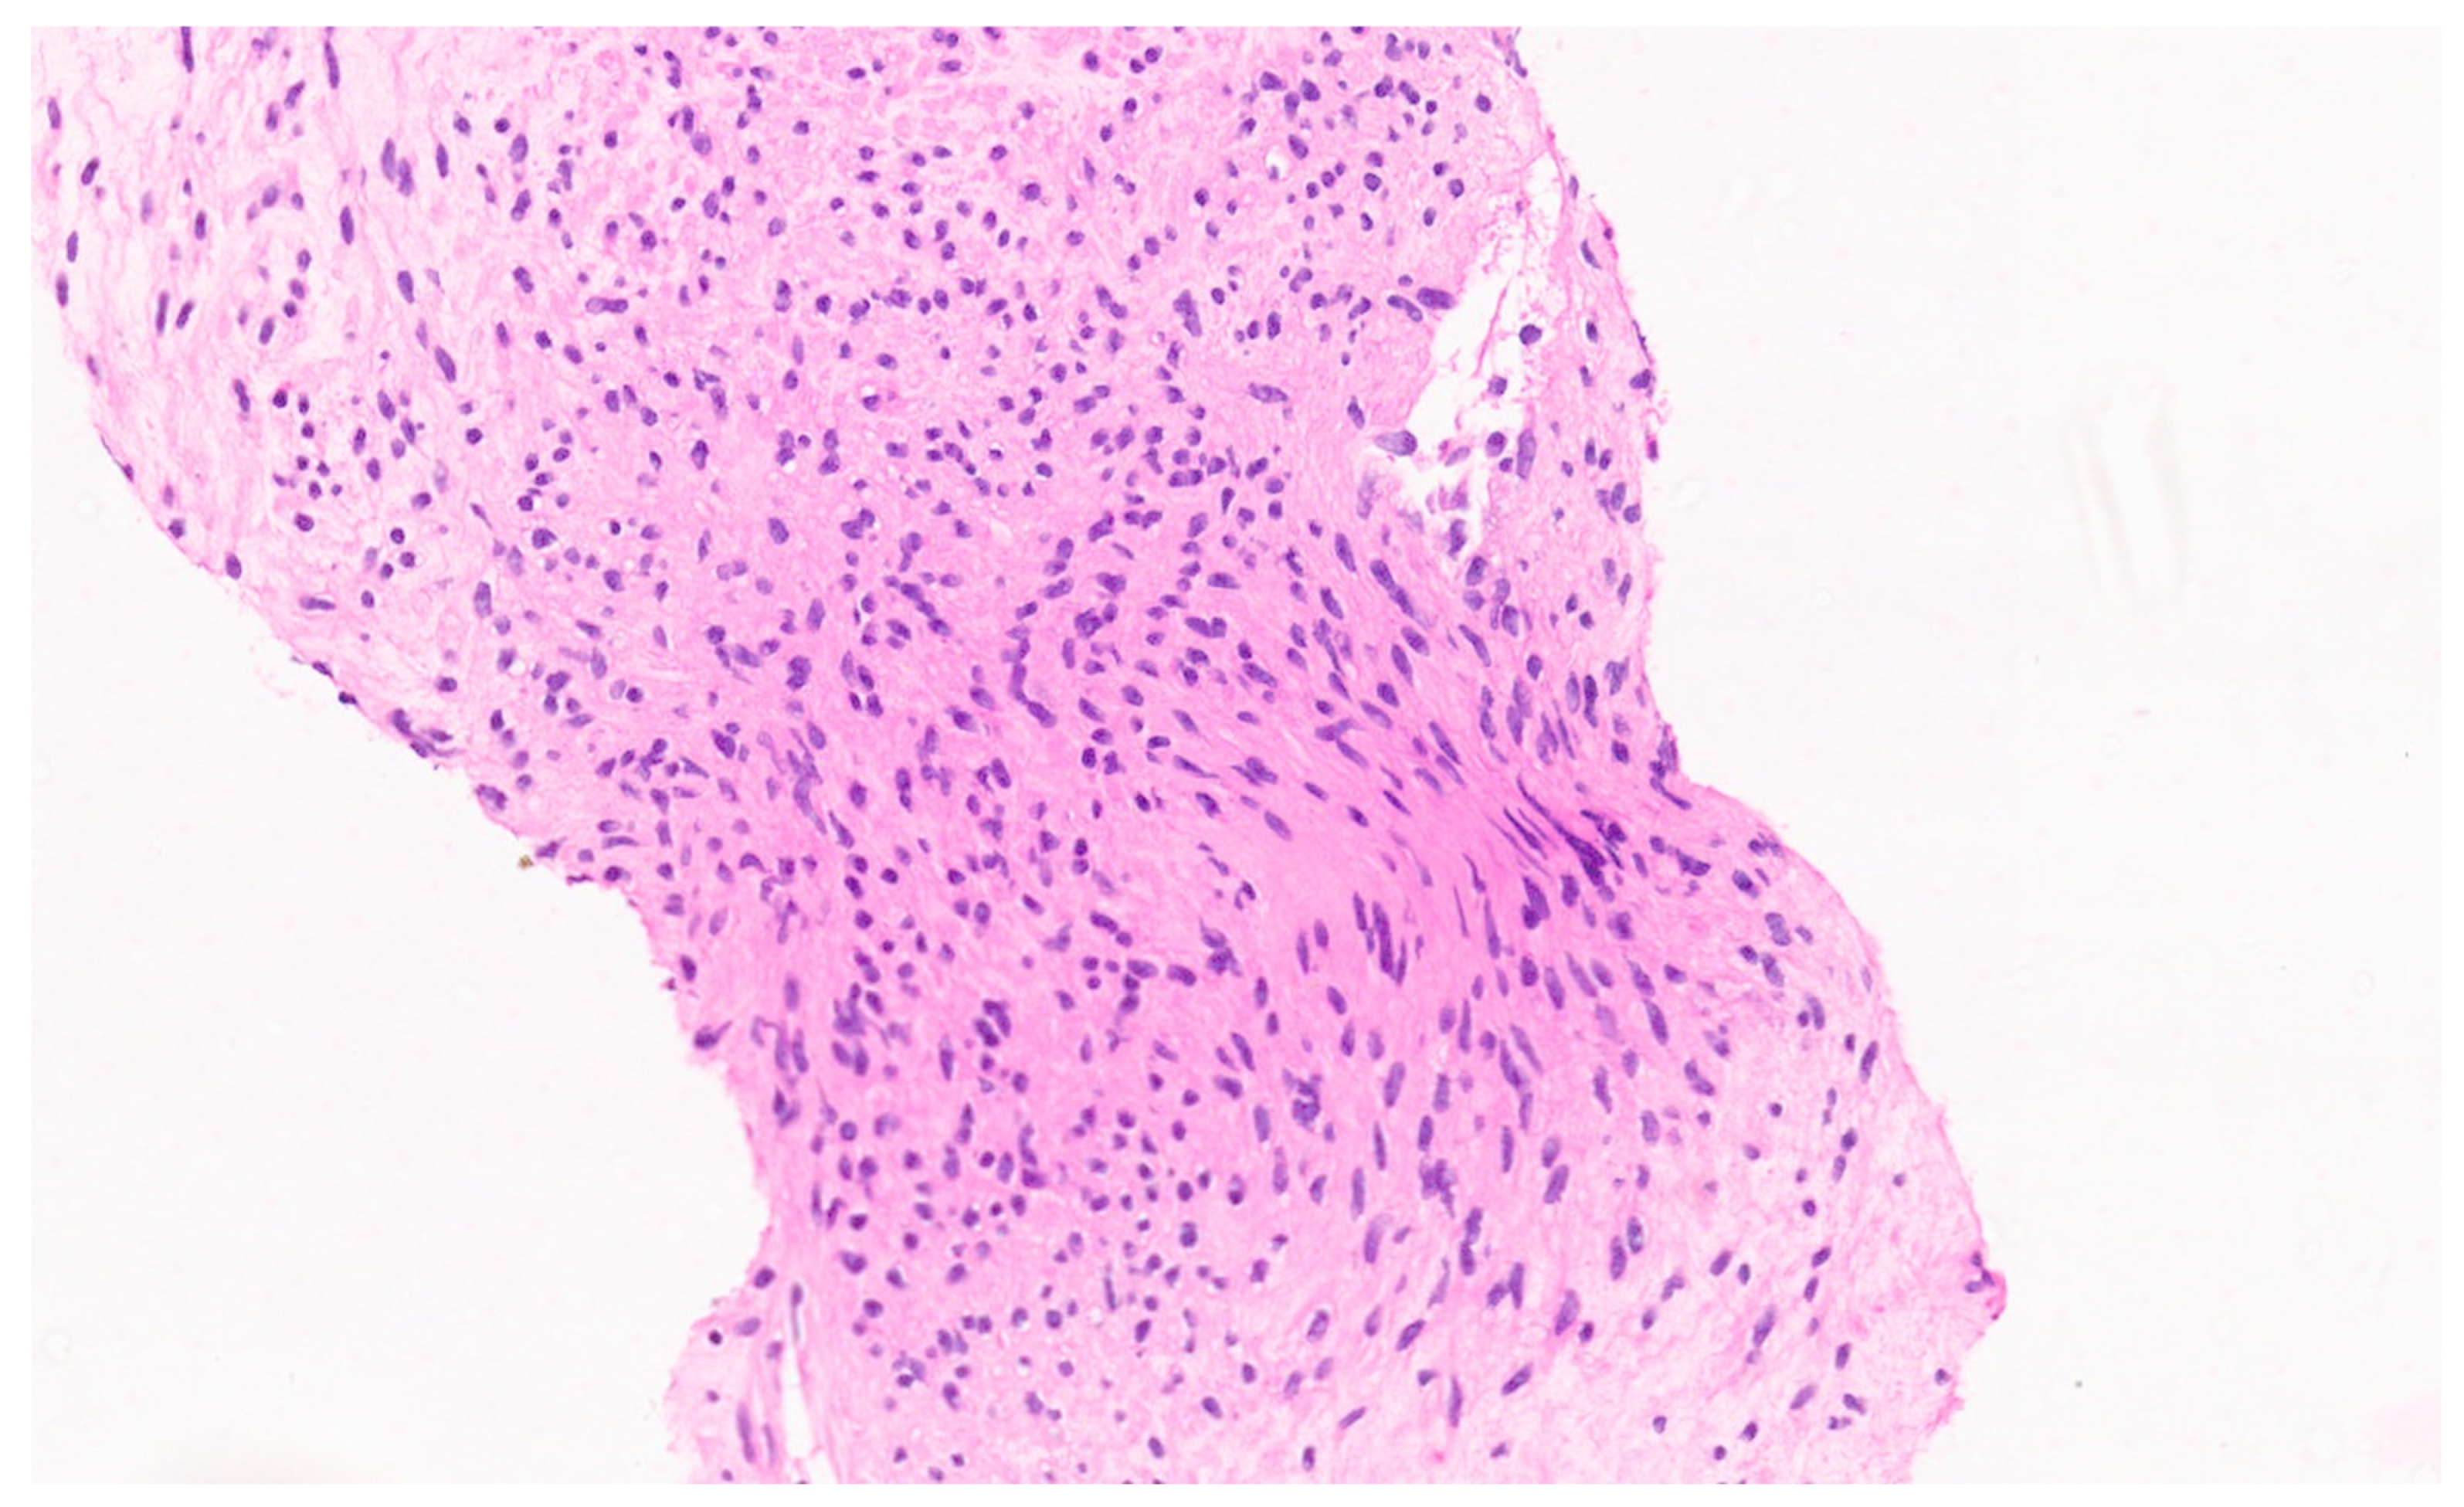

12.3. Pathology